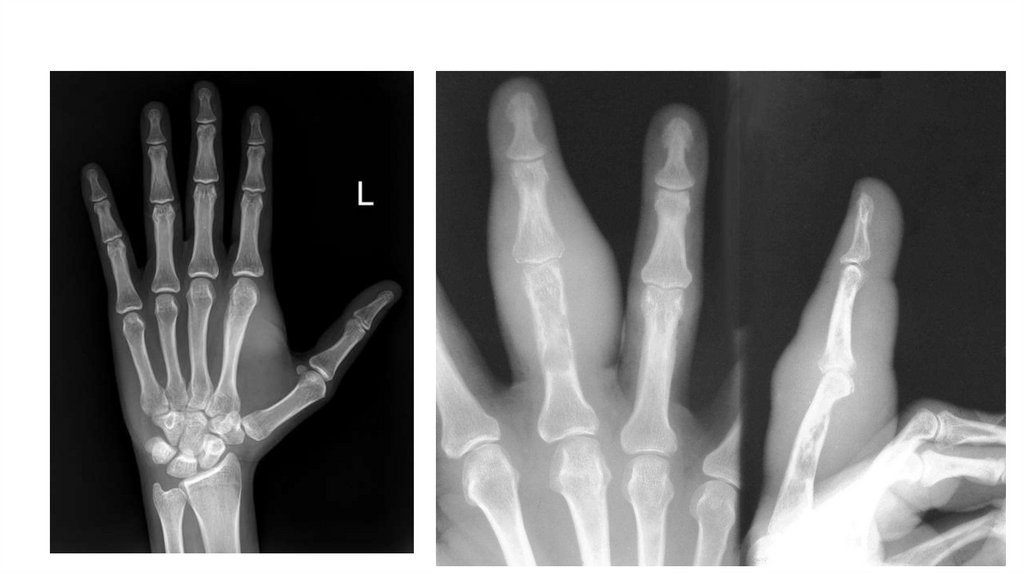

Воспалительные заболевания опорнодвигательного аппарата

«Воспалительные

заболевания опорнодвигательного аппарата»